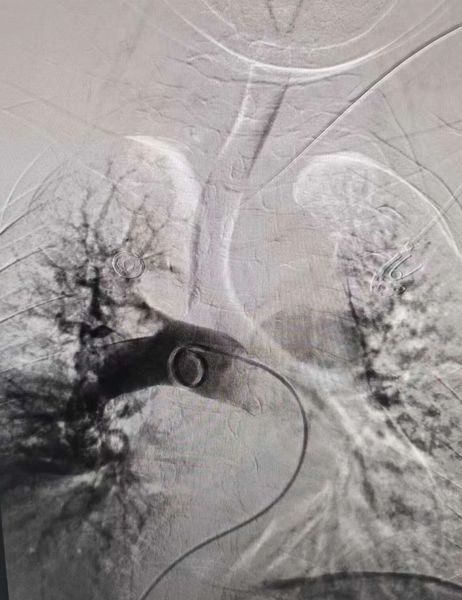

右肺动脉术后造影:闭塞血管开通

右肺动脉血管开通仍见较大血栓影